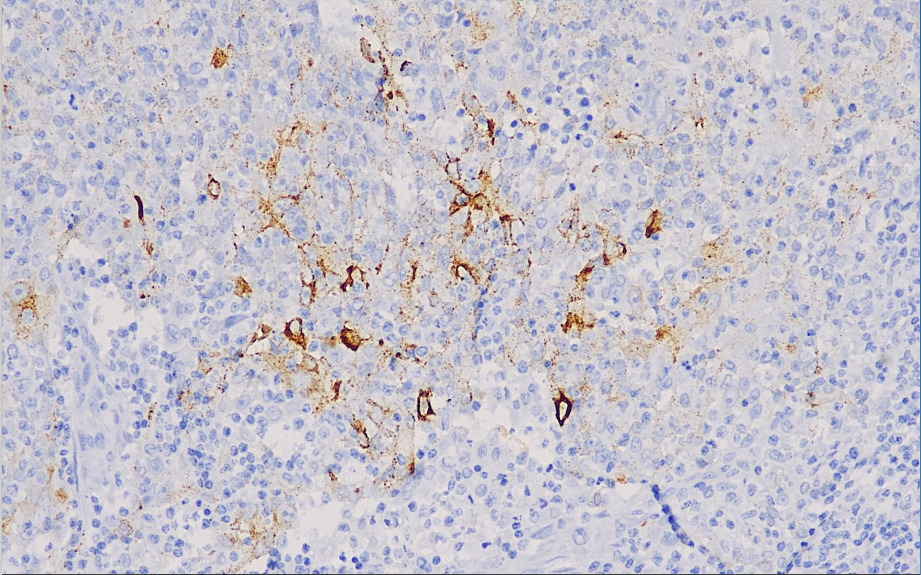

Positive control: EBV infected tissue

Epstein-Barr virus (EBV) is a human herpesvirus associated with many tumors. Such as nasopharyngeal carcinoma, infectious mononucleosis, gastric cancer, Bukitt lymphoma, Hodgkin lymphoma, angioimmunoblastic T-cell lymphoma, lymphomatoid granulomatosis, nasal T/NK lymphoma, post-transplantation lymphoproliferative disorders and smooth muscle tumors, AIDS disease-associated lymphomas, and innate immunodeficiency-associated lymphomas. EBER in situ hybridization of paraffin sections is the most sensitive method to detect EBV. However, the high protein content of the EBV membrane latent protein LMP-1 in classic lymphomas and lymphomatoid granulomatosis still allows immunohistochemistry to show EBV infection.

EBV antibody reagents can specifically bind to EBV molecular antigens. Immunohistochemistry kits containing EBV antibody reagents are suitable for the auxiliary diagnosis of EBV infection and certain tumors associated with EBV infection (such as poorly differentiated nasopharyngeal carcinoma, Hodgkin's disease, certain non-Hodgkin's lymphomas, etc.).